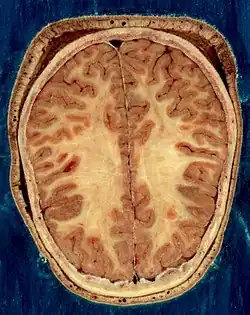

- ↑ Del Proyecto "Humano Visible" (Visible Human Project de la Biblioteca Nacional de Medicina de Estados Unidos. En este proyecto, dos cadáveres humanos (de un hombre y una mujer) fueron congelados y luego cortados en láminas delgadas, que fueron fotografiadas y digitalizadas individualmente. Esta sección está tomada a una pequeña distancia de la parte superior del cerebro, y muestra la corteza cerebral (la capa celular plegada al exterior) y la sustancia blanca subyacente, que consiste en tramos de fibra mielinizada que viaja hacia y desde la corteza cerebral.